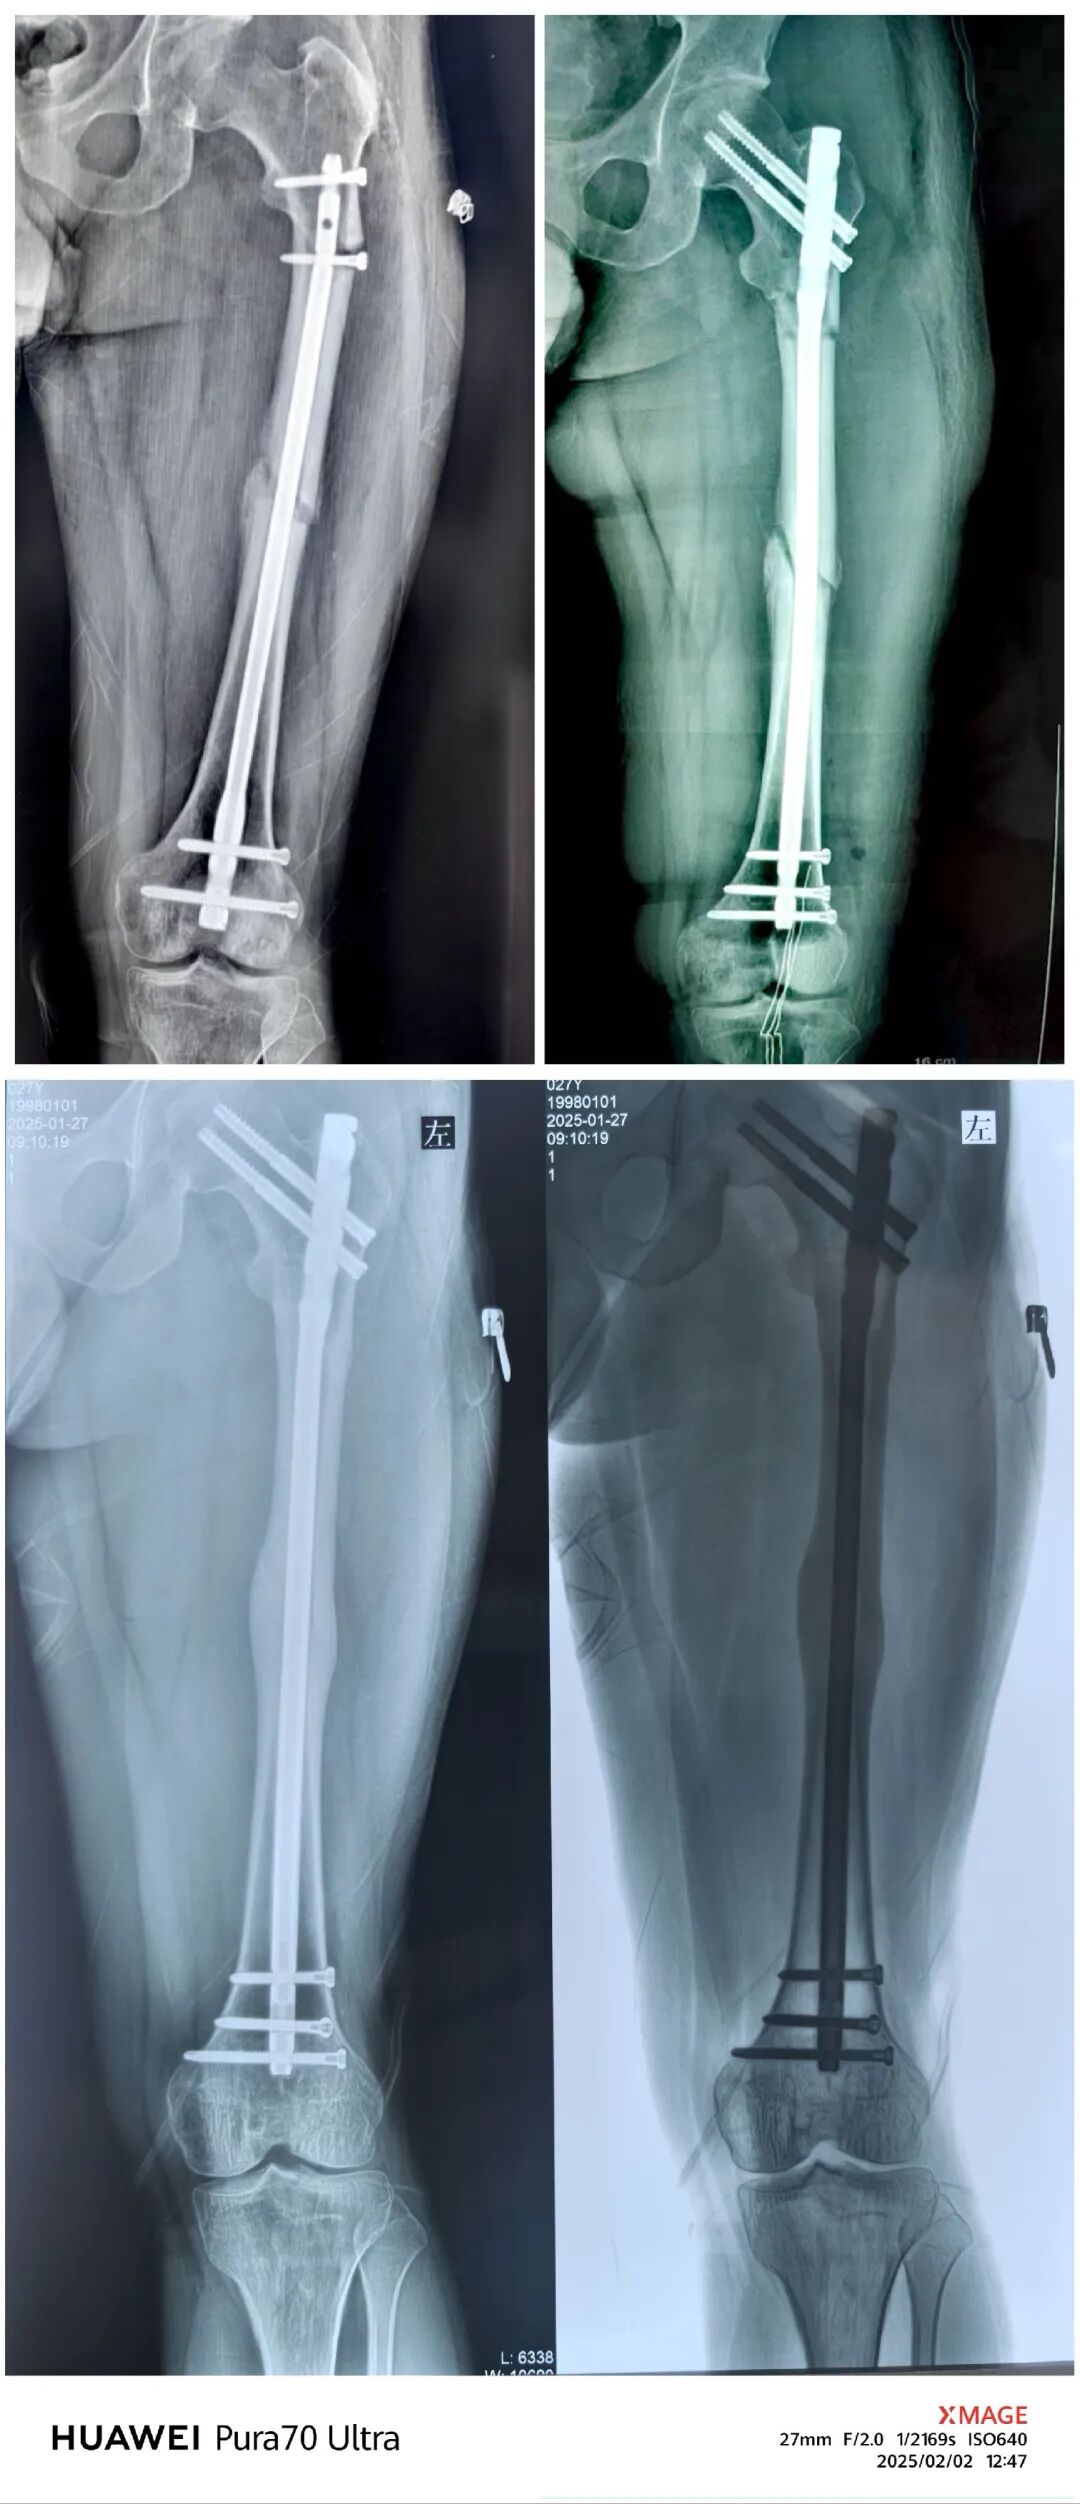

青年男性,股骨干骨折,切开复位,逆行髓内钉

逆行髓内钉:距膝关节间隙20 cm以内的骨干骨折、股骨髁上及髁间骨折。

术后3个月,弃拐负重,正常上班

取出内固定,恢复自由身